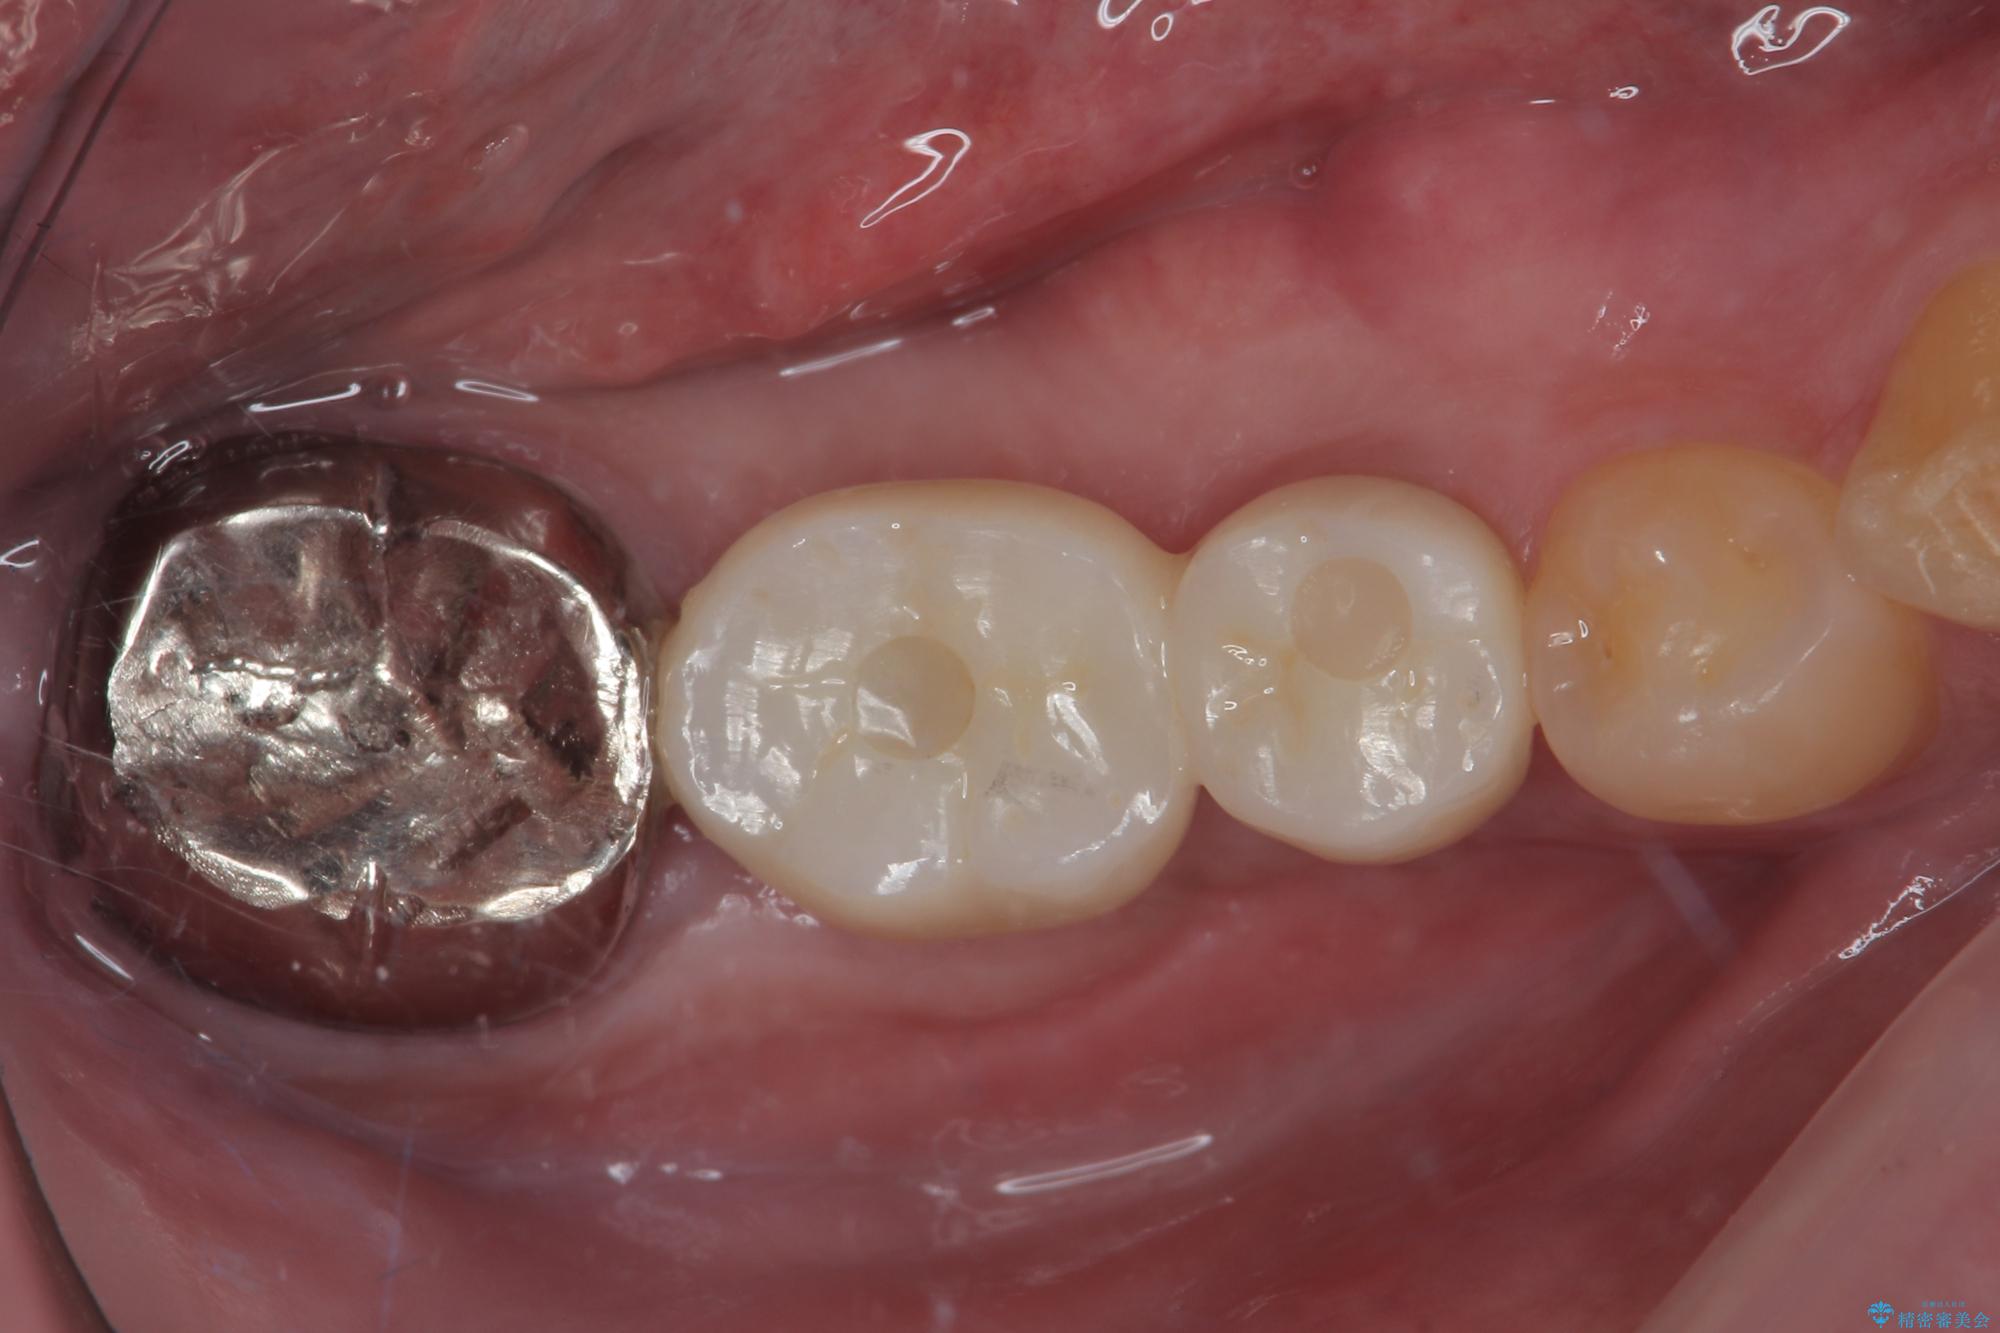

- むし歯を放置したことで、歯茎で膿が腫れ上がったしまったとのことで来院された患者様です。

ブリッジの支台歯が痛みを覚え、近医でブリッジを切断してもらって以降、そのままにしてしまったとのことでした。

問題が起きていた手前の歯から膿が出てきたことを自覚して当院を来院されましたが、既に歯根破折をしており、抜歯が必要な状態でした。

咬合力が非常に強い患者様であり、2歯欠損のブリッジ(しかも大臼歯は失活歯)は歯根破折のリスクが高すぎると判断し、抜歯部および欠損部に対して、インプラントによる補綴治療を行うこととしました。